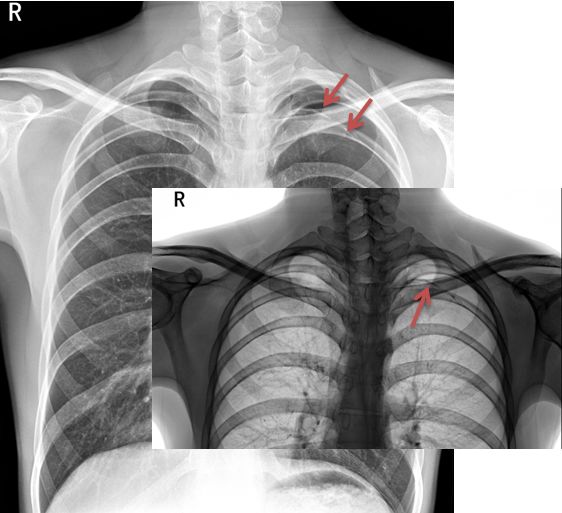

病例2

病例2患者的X线胸片

黑色区域:无肺纹理区域。肺叶压缩约70%;

蓝色虚线:被压缩肺组织边缘;

紫色箭头:肋膈角可见液-气平面;

橙色实线:第3、4肋骨前端骨桥关节,肋骨骨桥(先天变异);

可见心影及纵隔向对侧轻度移位。